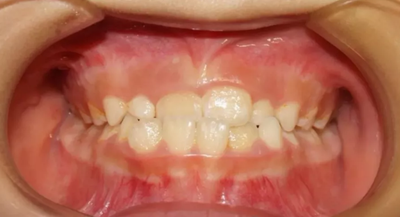

02 下頜后縮

因“沒有下巴”“臉型短”前來就診,該如何避免?